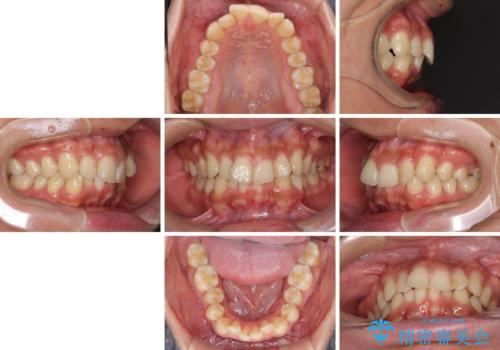

- 上下前歯のデコボコを気にして来院された患者様です。

全体的に叢生は軽度であったため、インビザラインにて矯正治療を行うこととしました。